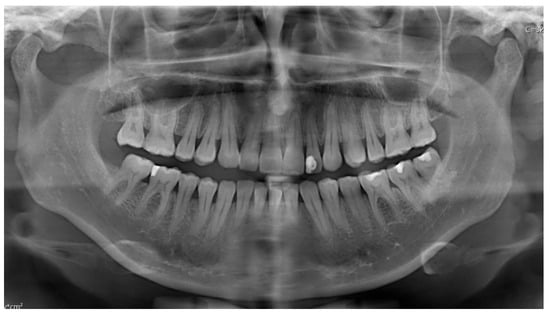

| 1 | Male | 48 | Osteoma of the coronoid process |

OPG CT | 19 mm | Coronoidectomy | 39 mm |

| 2 | Female | 10 | Bilateral hyperplasia of the coronoid processes |

OPG CT | 17 mm | Bilateral coronoidectomy | 45 mm |